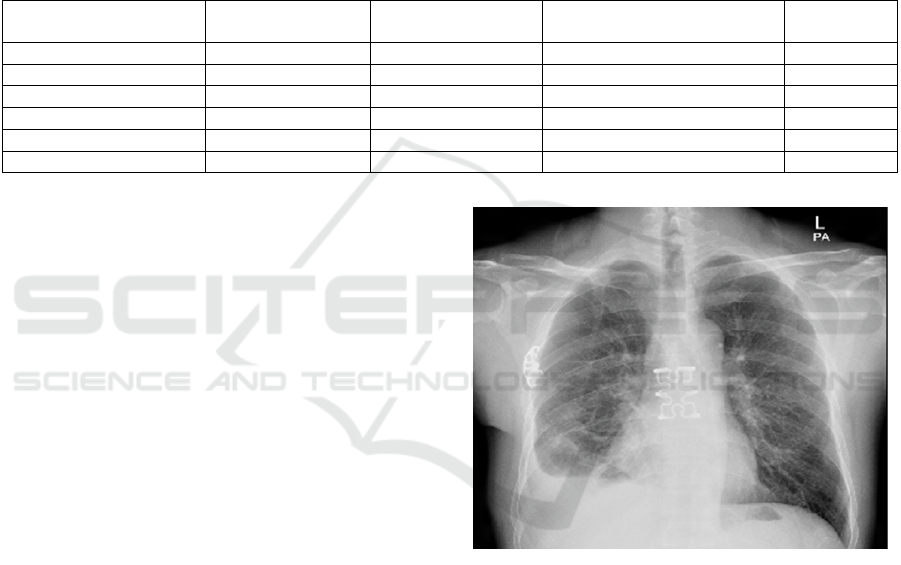

experiment can be done. In this paper, take the

medical field as an example, input an X-ray chest

photo. The photo is shown in Figure 2.

Figure 2: X-ray Chest Picture. (Youlai Doctor, 2024)

Ask the question Does this patient have steel

nails in his chest, reply in Chinese. Under the

repetition penalty parameter 1.2, the model

recognizes a steel nail in the patient's chest and adds

that it may be a tool for fixing the chest wall during

treatment or surgery; under parameter 1.5, the

previous output remains unchanged, but the sentence

X-ray shows L-1023 is fictionalized at the end.

If the model is not prompted, but is simply asked,

Do you know what is wrong with this patient?, the

model assumes that the patient has small nodules and

masses in the lungs.

This experiment illustrates a number of points.

One is that the repetition penalty parameter 1.5 would

fudge the content and is not suited to the rigors of the

medical field; the other is that the model's image

parsing is so powerful that it is able to identify foreign

objects in the chest cavity on monochrome X-rays,

even though it requires some prompting to

identifythem as steel nails, which only shows that the

model has not been trained in the medical field. What

is certain is that lightweight models have unlimited

potential for future deployment in various domains.